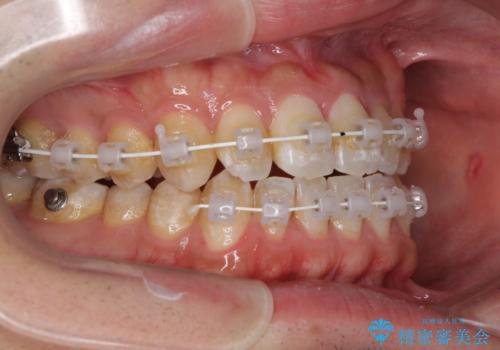

- 矯正装置

- 審美装置

- 1年

- 10-30回